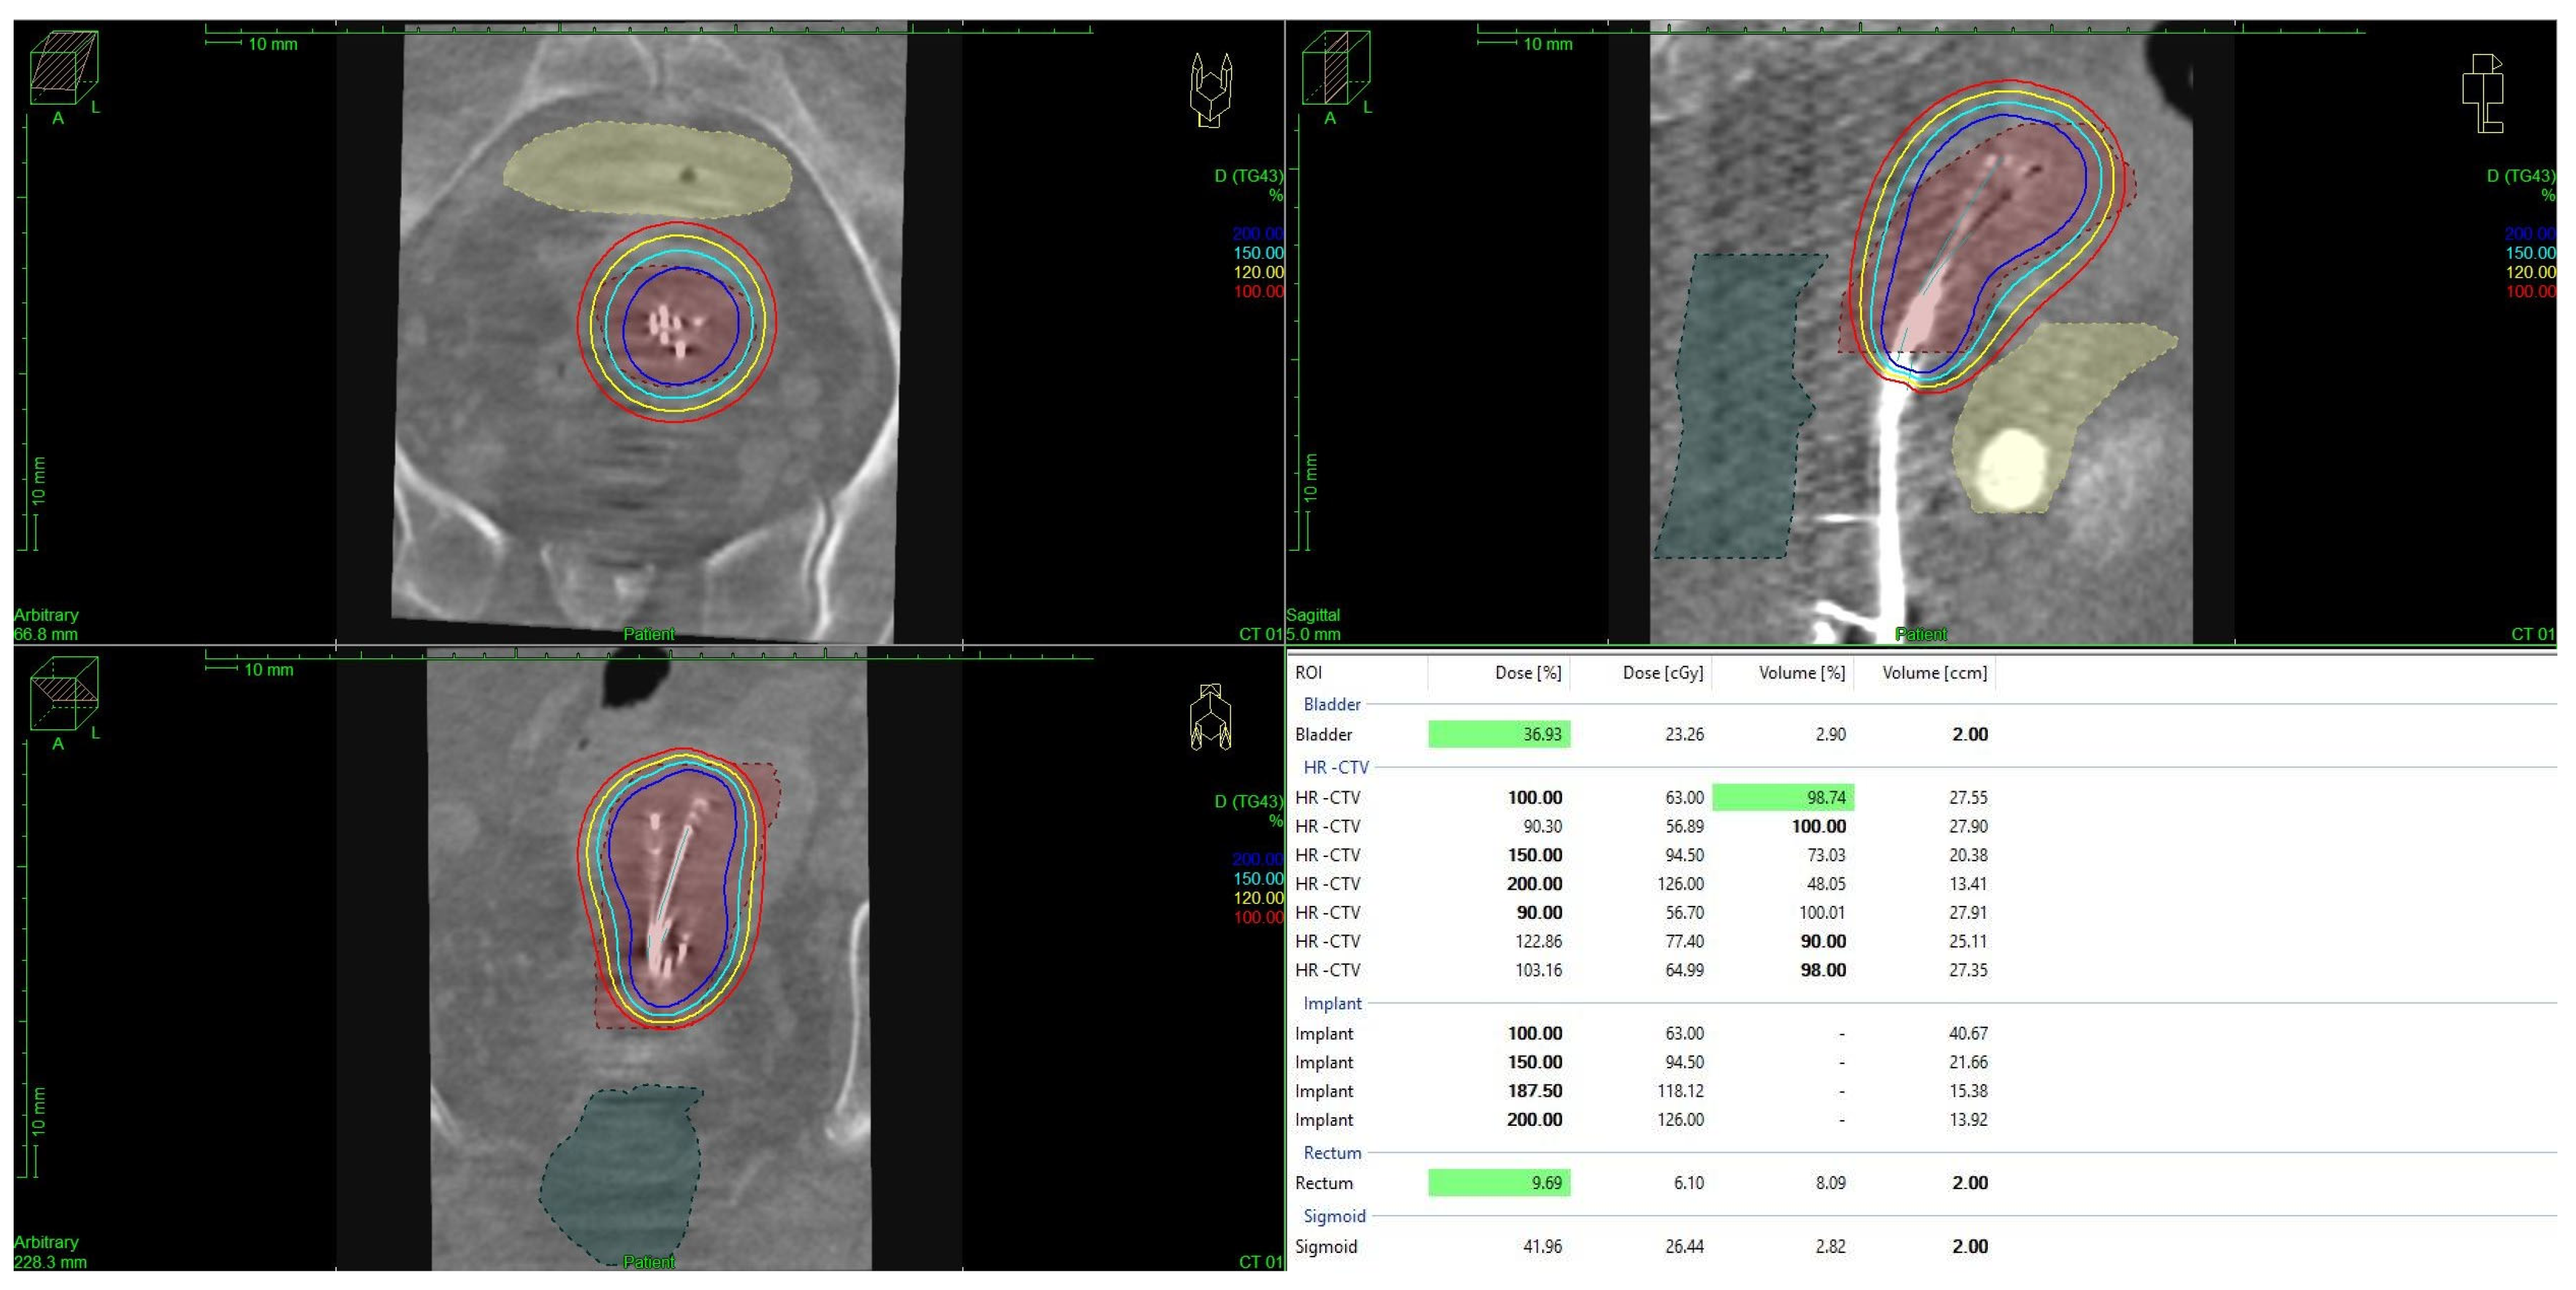

For both HDR- and PDR-brachytherapy, the dose constraints for organs at risk were set to a D2ccm (dose the most exposed 2ccm of the structure receives) of <75 Gy for the rectum and <85 Gy for the bladder, respectively. Dose calculation and treatment planning for brachytherapy was performed using TPS Plato and Oncentra Brachy (Nucletron, The Netherlands), with dose distributions being optimized through geometrical and graphical techniques. The treatment plan evaluation was based on dose–volume histogram (DVH) metrics, including D90, D100, V100, and V150 for the target volume and D2ccm for the OARs, as mentioned above (see Figure 1).

Figure 1. Brachytherapy using Heyman packing techniques and dose distribution in a patient with endometrial cancer. Graphic created with Oncentra Brachy (Nucletron, The Netherlands).